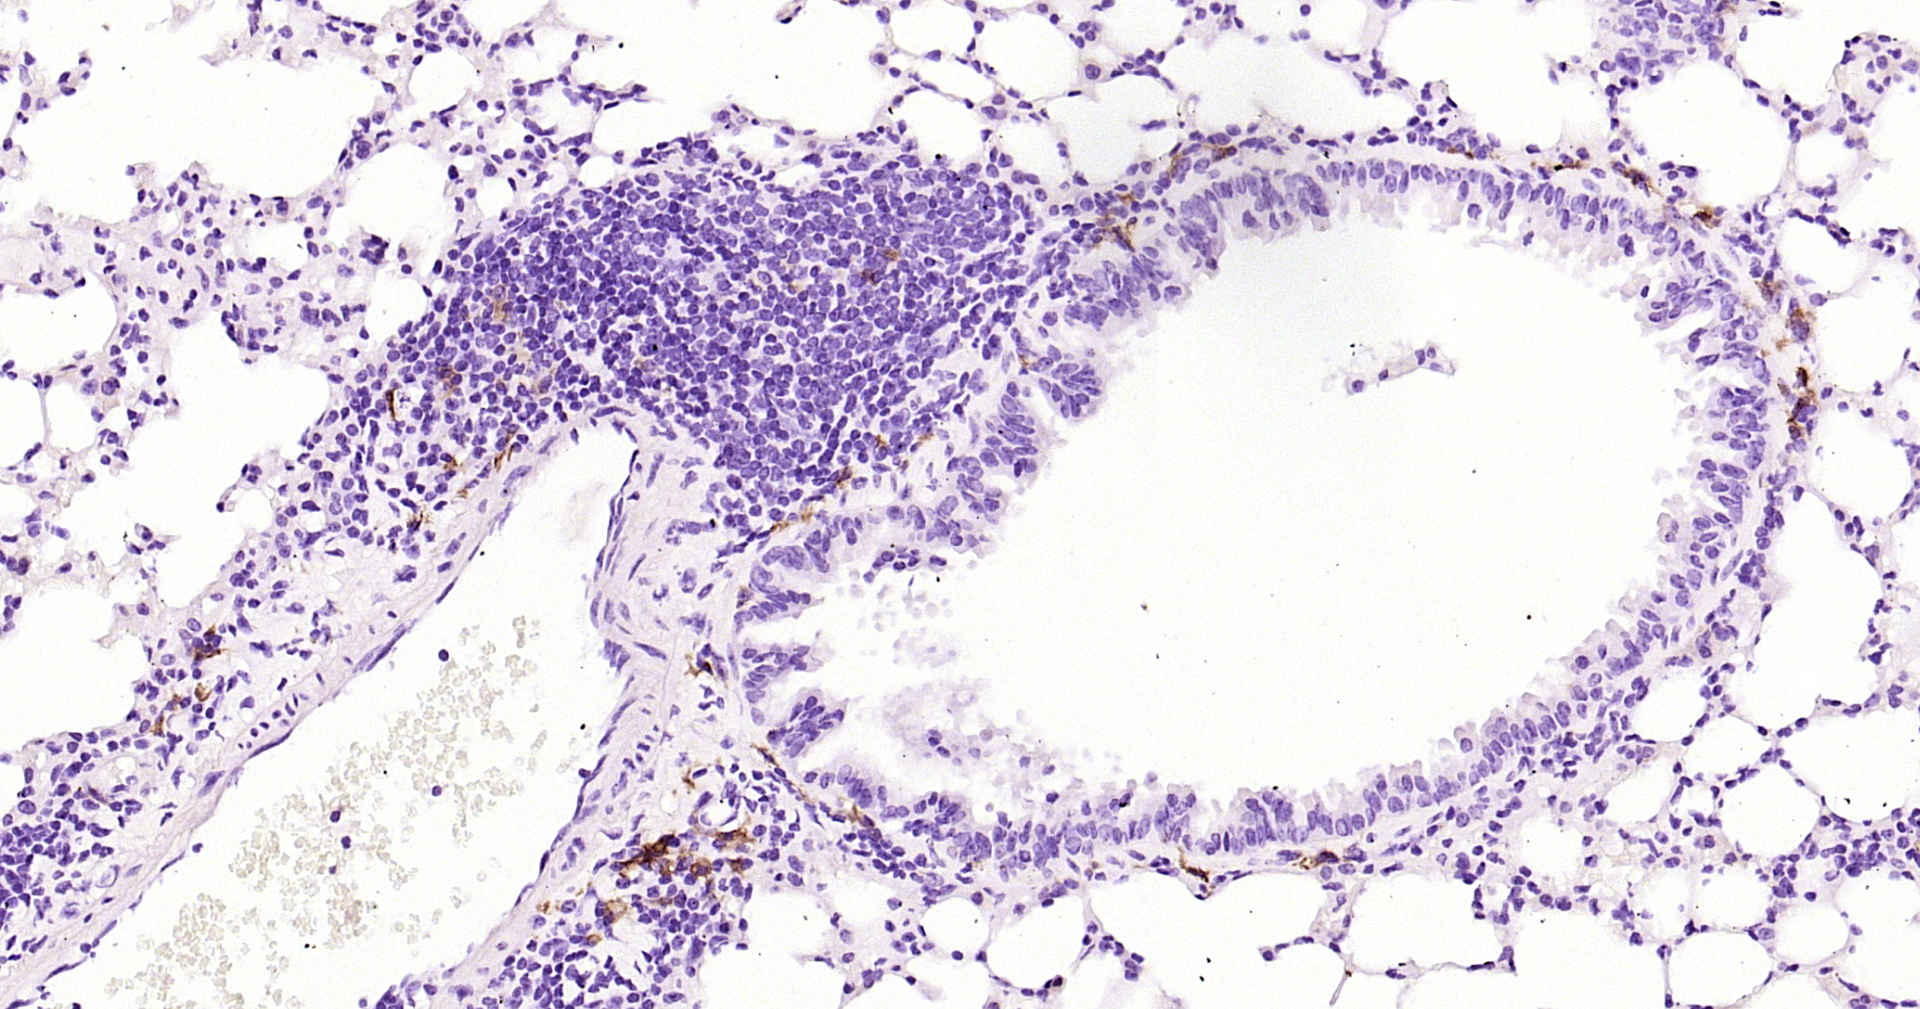

• IHC-P

• IHC

Application Dilution

IHC-P 1:200-400

IHC